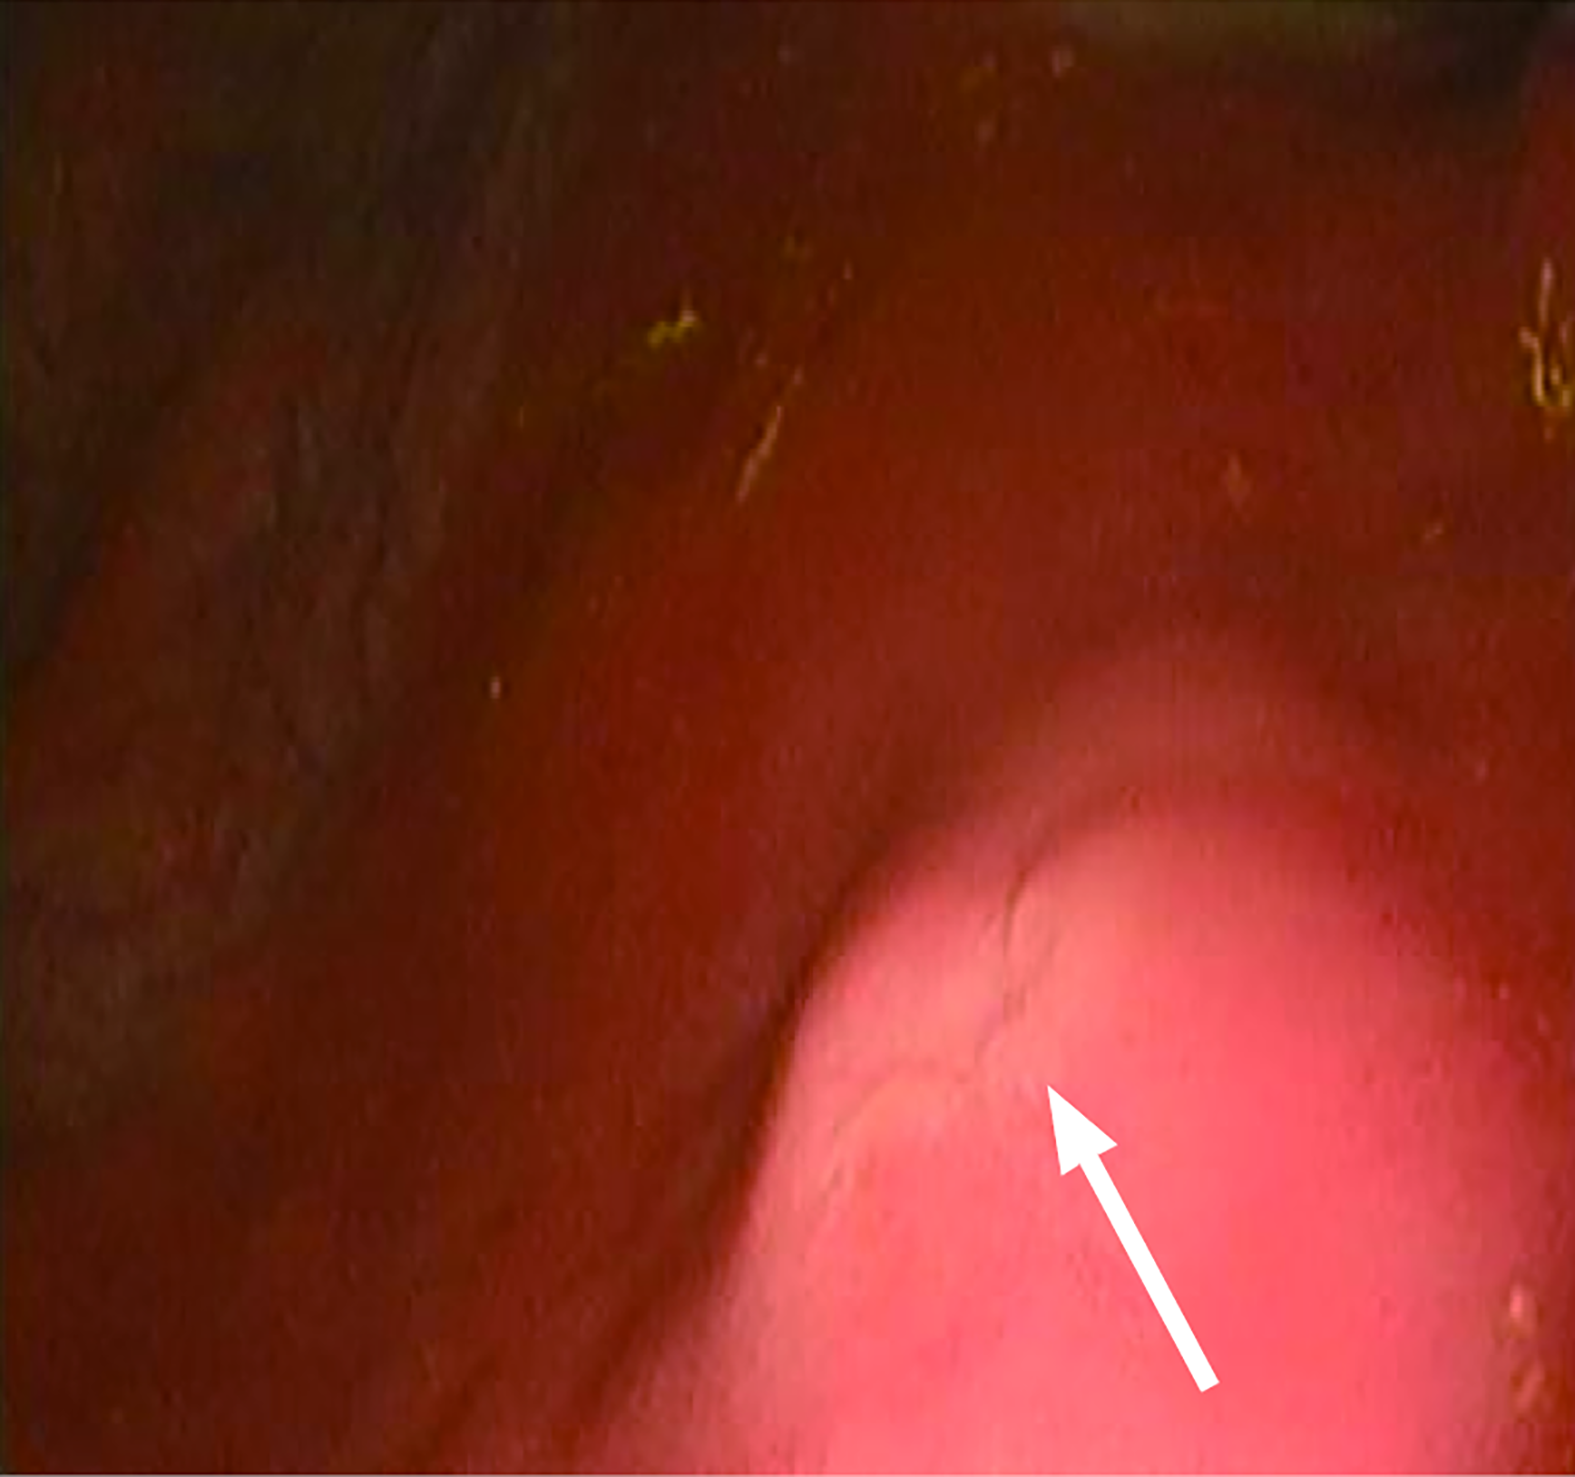

The core zone was constructed by three-dimensional bioprinting, comprising: A bottom layer of 8% gelatin methacryloyl (GelMA) infused with primary gastric smooth muscle cells (at a density of 1 × 106 cells per milliliter of GelMA); a top layer of 8% GelMA incorporated with gastric epithelial organoids (at a density of 1000 organoids per milliliter of GelMA). It has achieved certain results in animal experiments. We made a 1-cm gastric wound in a porcine model and then collected endoscopic view of the repair site at 2 weeks after applying the biopatch (Figure 2). This patch utilizes a biological mesh framework to attempt multi-layer repair of full-thickness gastric defects, which is expected to facilitate multi-layer repairs such as the repair of gastric ulcer perforation. However, larger animal models are needed to verify this, and in the future, digestive endoscopic delivery will be explored to promote wound closure and repair.